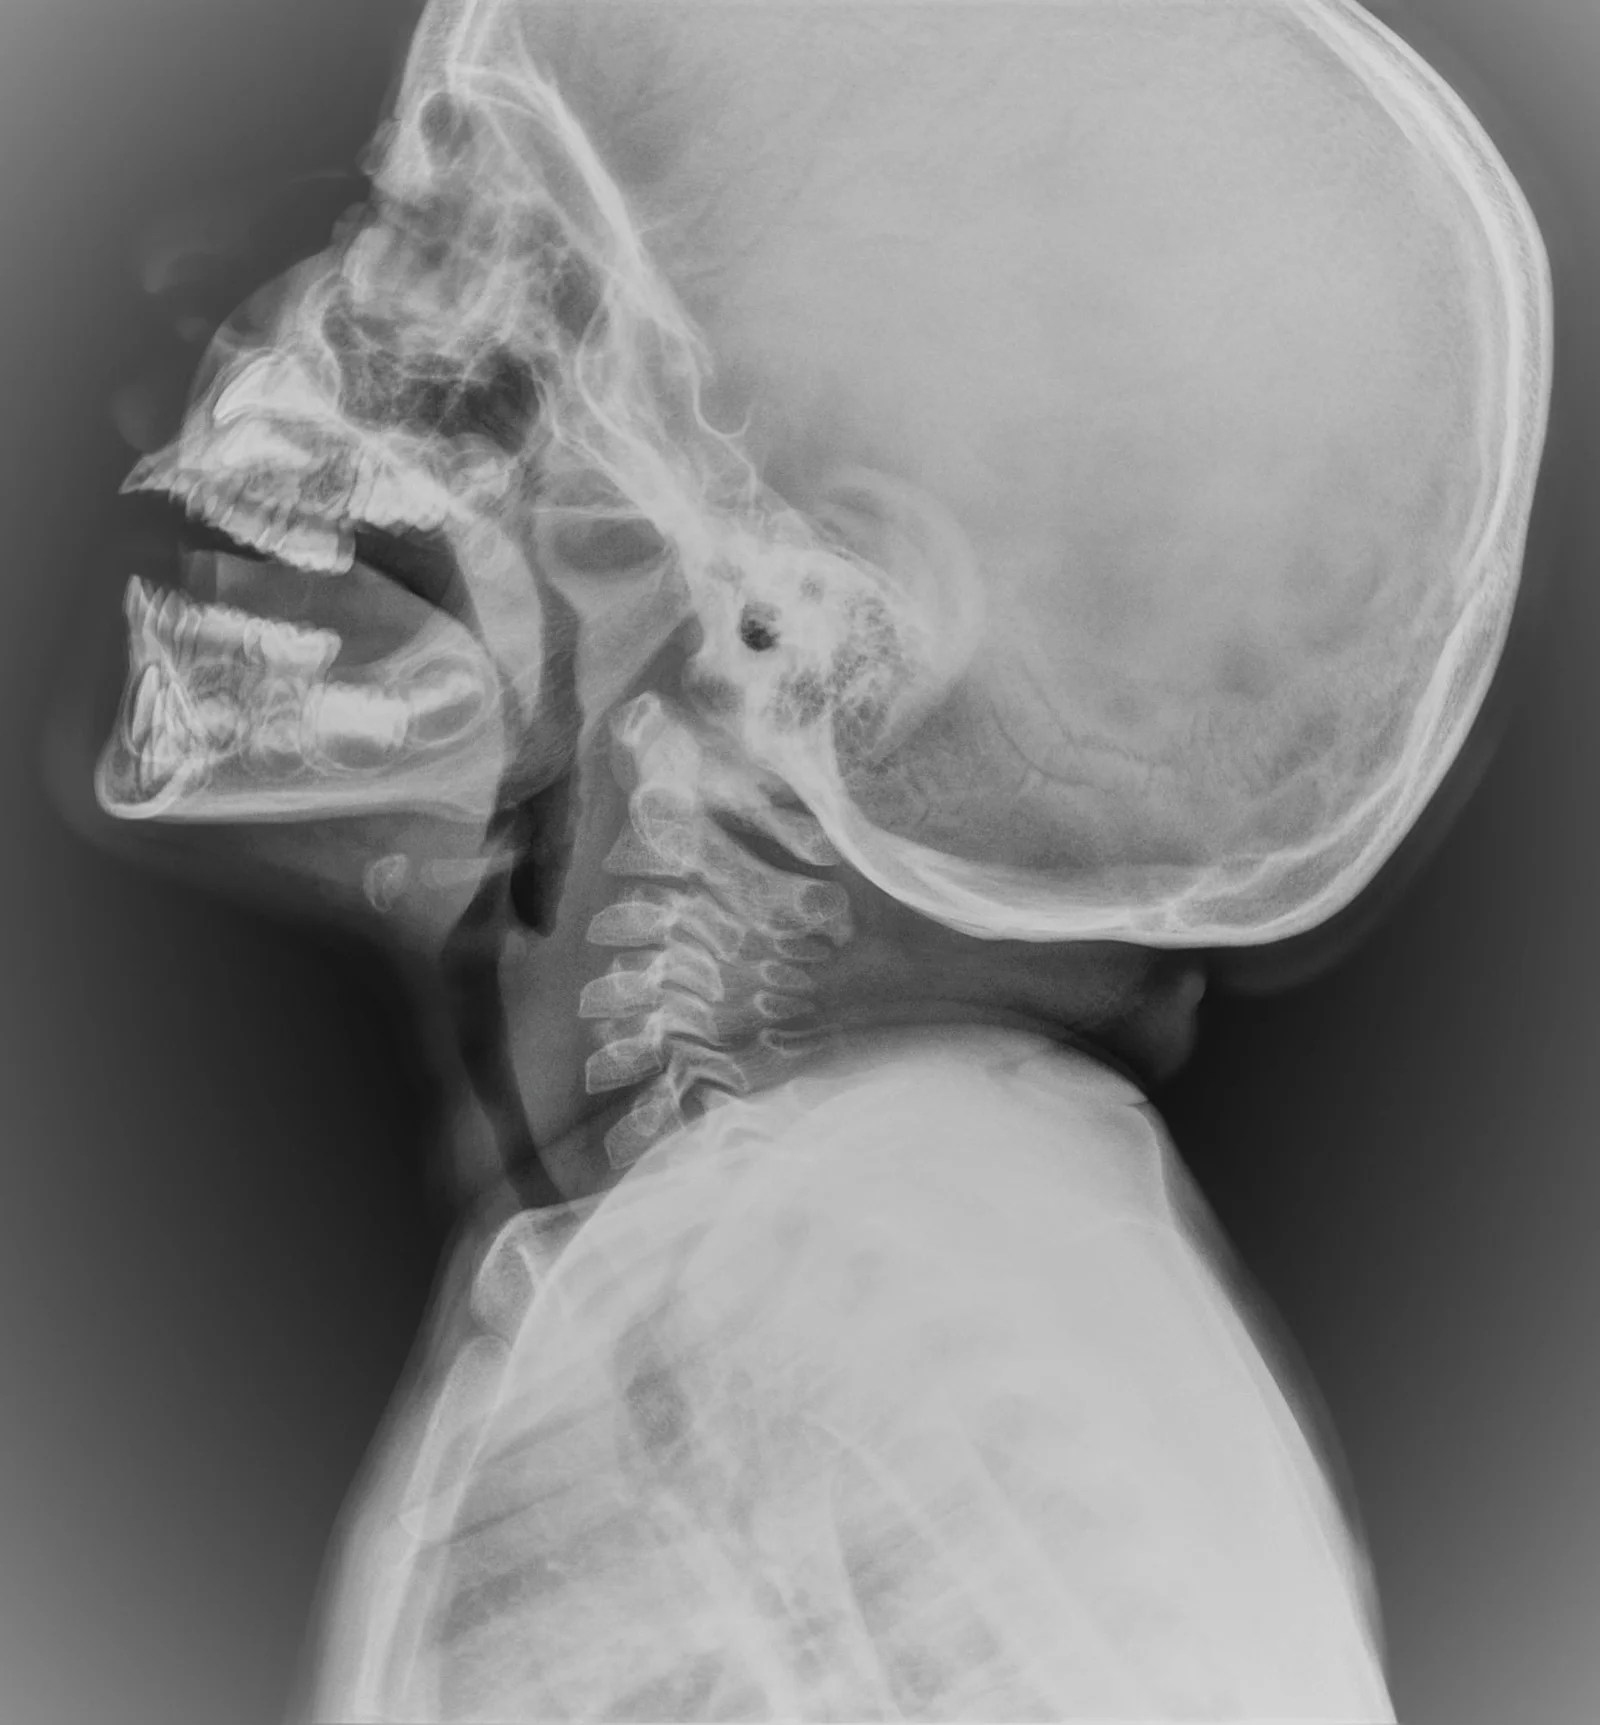

Adenoids Xray Grommets For Adenoids Adenoids are small lumps of tissue at the back of the throat behind. if large adenoids are causing ongoing problems, your doctor may recommend an adenoidectomy. A child’s adenoids can sometimes become swollen and, occasionally, infected. the adenoids are fleshy lumps of tissue that are located at the back of the inside of the nose and at the. Grommets For Adenoids.

Adenoids Xray Grommets For Adenoids the adenoid is a proliferation of lymphoid tissue lining the posterior wall of the nasopharynx, forming the superior aspect of waldeyer’s lymphatic. an adenoidectomy is an operation to remove enlarged adenoids. Is there an age limit for adenoidectomy? what are the benefits of adenoidectomy? if large adenoids are causing ongoing problems, your doctor may recommend an. Grommets For Adenoids.

Adenoids Xray Grommets For Adenoids what are the benefits of adenoidectomy? an adenoidectomy is an operation to remove enlarged adenoids. the adenoid is a proliferation of lymphoid tissue lining the posterior wall of the nasopharynx, forming the superior aspect of waldeyer’s lymphatic. A child’s adenoids can sometimes become swollen and, occasionally, infected. Adenoids are small lumps of tissue at the back of. Grommets For Adenoids.